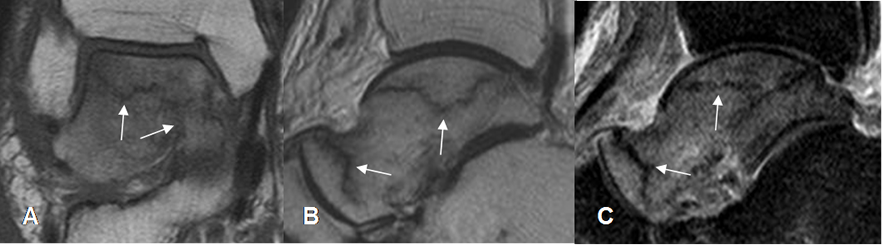

Fig 33. Fractura del talo.

A: RM coronal y B: RM sagital en T1. Talo hipointenso, con fracturas lineales.

C: RM sagital en STIR Edema óseo y confirmación de las fracturas lineales.